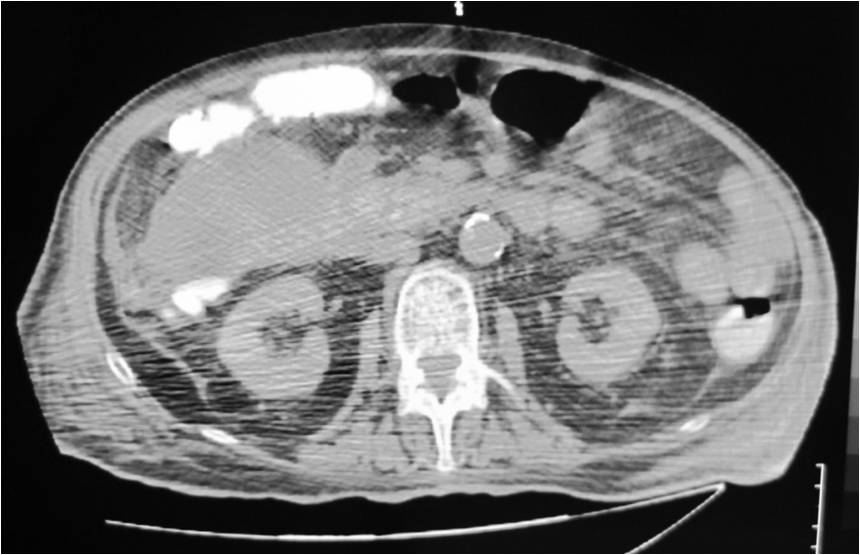

- Right sub diaphragmatic abscess post right hemicolectomy

- Successful drainage